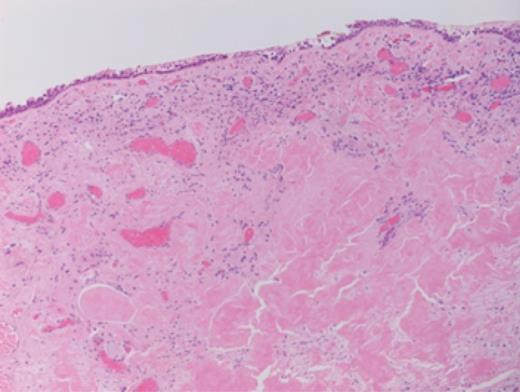

Histopathology revealed prominent acellular, eosinophilic deposits within the stroma (Figs 1 and 2). Under polarized light, Congo red staining showed the characteristic apple-green birefringence of amyloidosis. No dysplasia or malignancy was seen.

Congo red staining of the biopsy sample. Histology shows an acellular, amorphous, eosinophilic material deposit in the stroma, with perivascular and periglandular accentuation. Typing of the specimen is based on clinical and laboratory findings (including paraproteinaemia looking for an underlying myeloma, TTR gene rearrangement studies looking for the genetic defect in familial amyloid.)